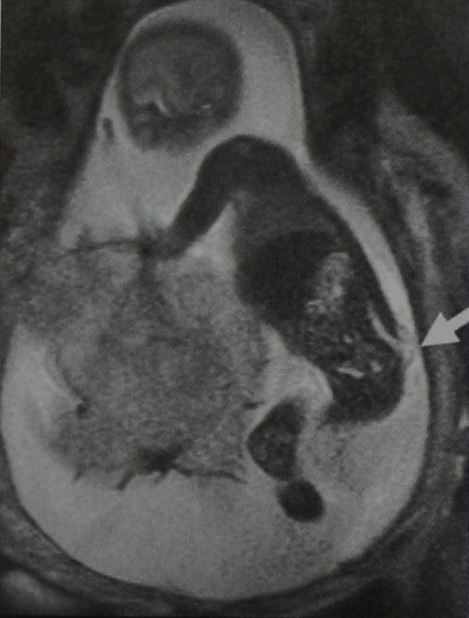

У новорожденного в области крестца выявлено объемное образование. Движения ног у ребенка не нарушены. МРТ пояснично-крестцовой области (сагиттальная проекция, Т2-взве- шенное изображение). Грыжевой мешок содержит только ЦСЖ. Наблюдается внутрипозвоночное опущение мозгового конуса и короткие прямые волокна конского хвоста, которые фиксированы к каудальным отделам дурального мешка.

МРТ позвонка Ц/ (горизонтальная проекция, Т2-взвешенное изображение). Костный дефект закрыт соединительнотканными структурами (данные получены во время операции), через которые выпячивается грыжевой мешок, заполненный ЦСЖ. Определяется перегородка, но нервные структуры отсутствуют. Эти структуры не выходят за пределы позвоночного канала. Переднее субарахноидальное пространство не расширено. Грыжевой мешок покрыт тонким слоем кожи.

При УЗИ в 20 нед. беременности выявлено наличие spina bifida. МРТ плода и таза (фронтальная проекция, Т2-взвешенное изображение). Грыжевой мешок, расположенный в крестцовой области и содержащий структуры спинного мозга, ориентирован вдоль верхушки крестца.

На Т2-взвешенном изображении в горизонтальной проекции визуализируются костный дефект с широким основанием и миелоцеле, содержащее структуры спинного мозга (стрелка).